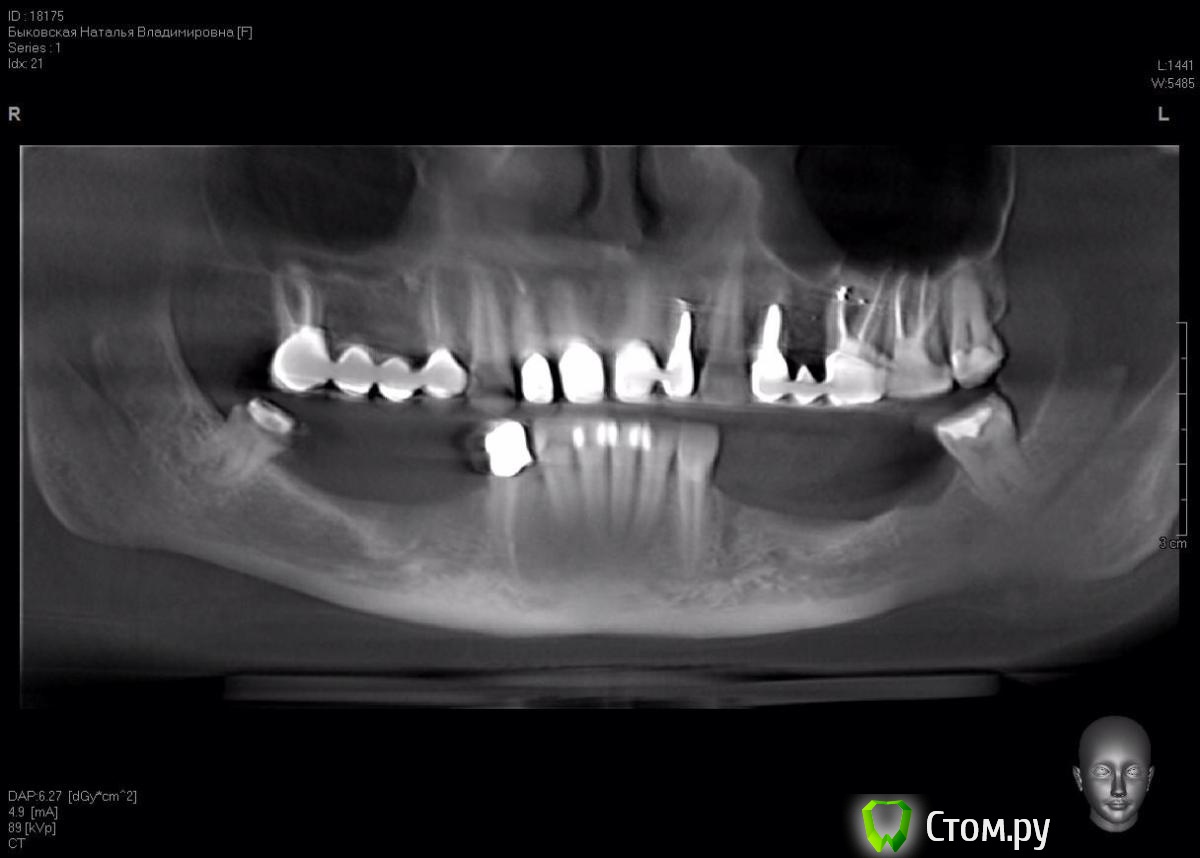

DoktorDre Опубликовано 8 октября, 2014 Поделиться Опубликовано 8 октября, 2014 (изменено) Коллеги - помогите. Имею небольшой опыт ламинатной техники, гбр , расщепления. Планируемая работа- импланты 44-46 и 34-36. Смущают дырки металисов.....как их обойти??? Хотел делать по Кури.Посоветуйте, опытные хирурги! Изменено 8 октября, 2014 пользователем DoktorDre Ссылка на комментарий

DoktorDre Опубликовано 8 октября, 2014 Автор Поделиться Опубликовано 8 октября, 2014 (изменено) Спасибо!Это все замечательно! Как обойти торчащие вверх металисы?? Не прикручу же на них ламинат!Особенно меня смущает 45-не расщепить, и металис совсем близко Изменено 8 октября, 2014 пользователем DoktorDre Ссылка на комментарий

DoktorDre Опубликовано 8 октября, 2014 Автор Поделиться Опубликовано 8 октября, 2014 Почему не расщепить? ,,,1) Будет сдавлен менталис в обл 45 2) много коркиткалки- плохо щепится 3) дефицит по вертикали только усугубится после расщепления 1 мм как правило уходит.. Ссылка на комментарий